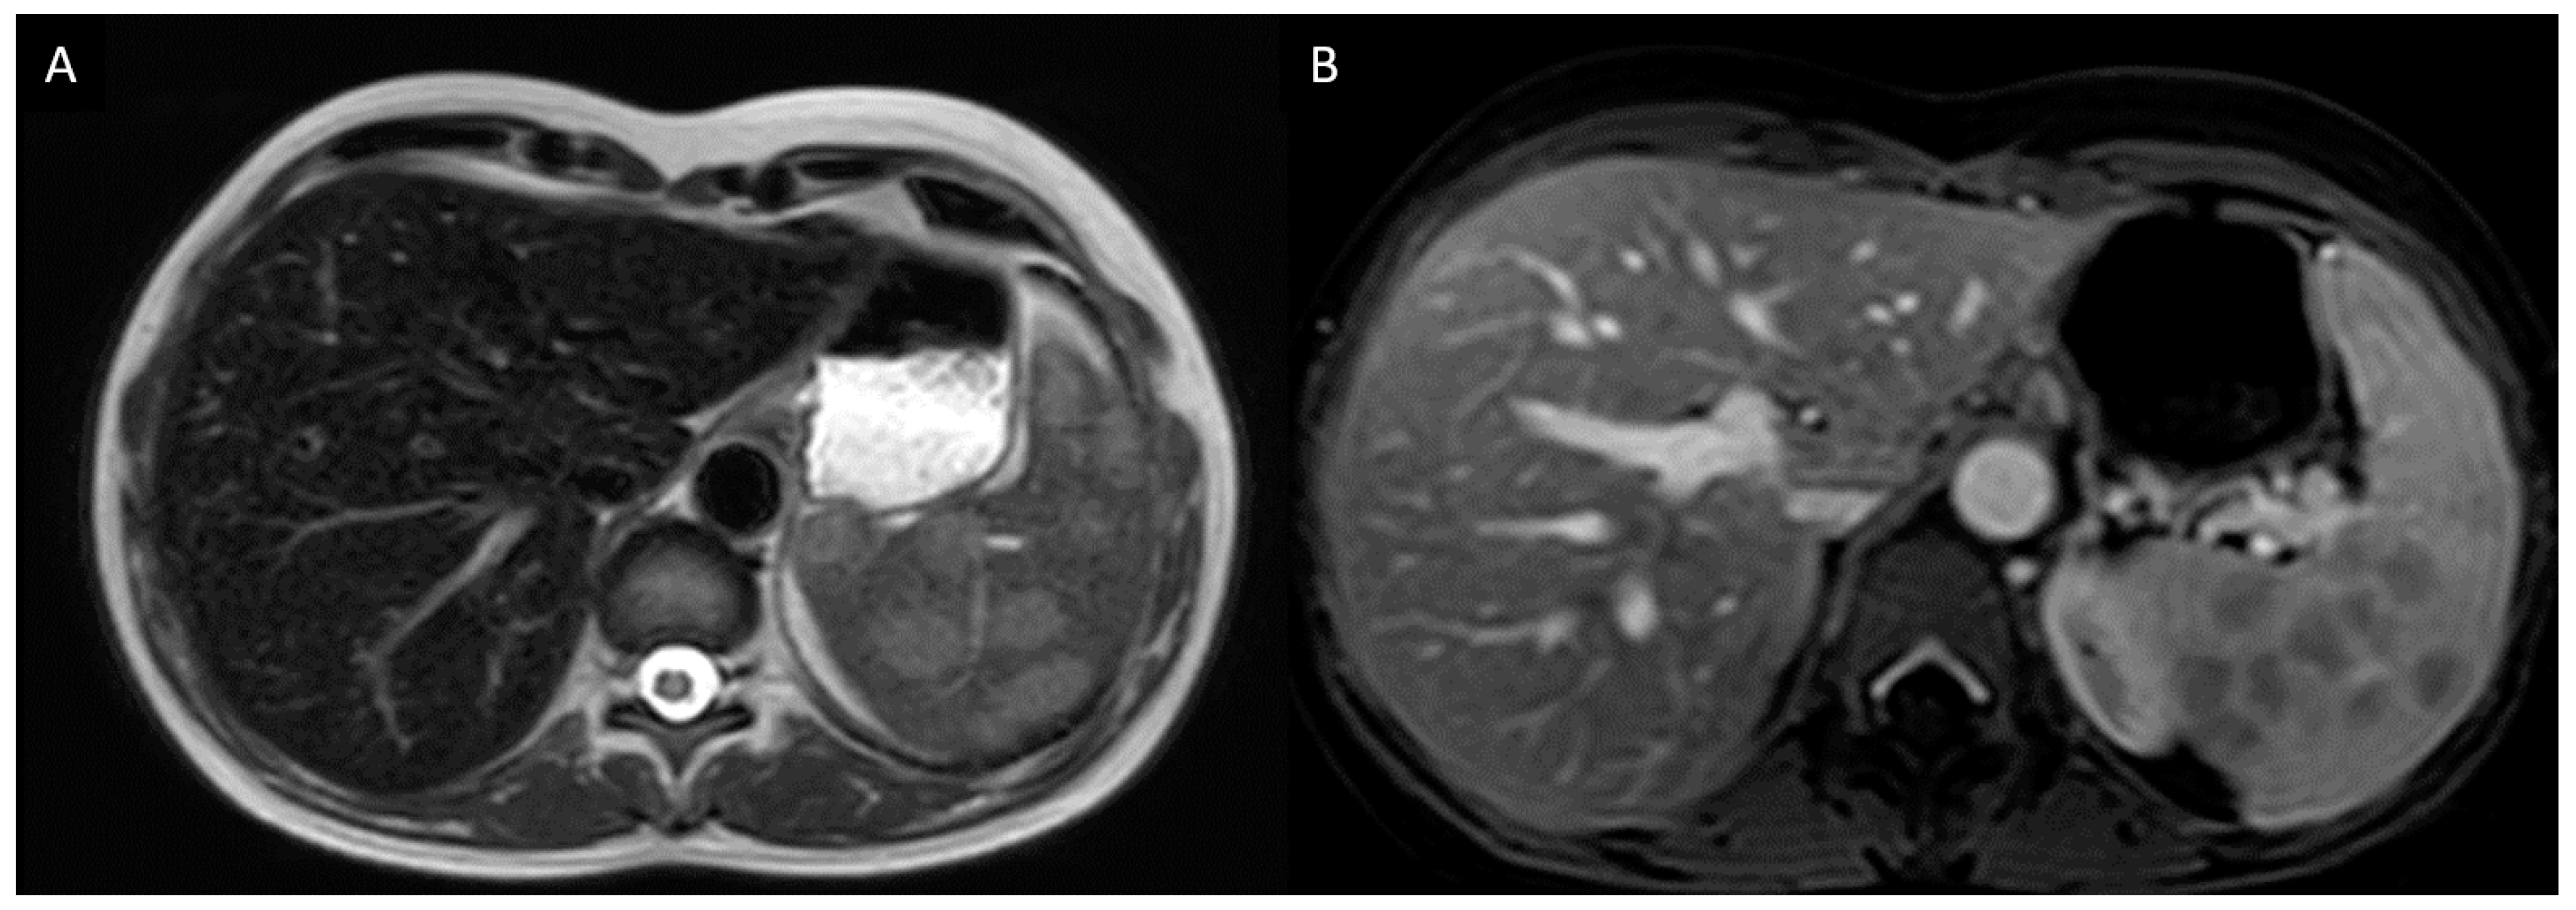

3.2.1. Case Description

| 7* | F | 63 | Caucasian | Bilateral anterior and intermediate uveitis. Granuloma on MSGB. Gait disturbance with multiple supra tentorial demyelinating lesions on FLAIR-weighted sequences. | Corticoresistant uveitis and neurological involvement. | 3 years | Vitroretinal lymphoma. | R-Metho AraC chemotherapy followed by ibrutinib and R-VP16-Holoxan. | The patient died 3 months after the diagnosis [204]. |